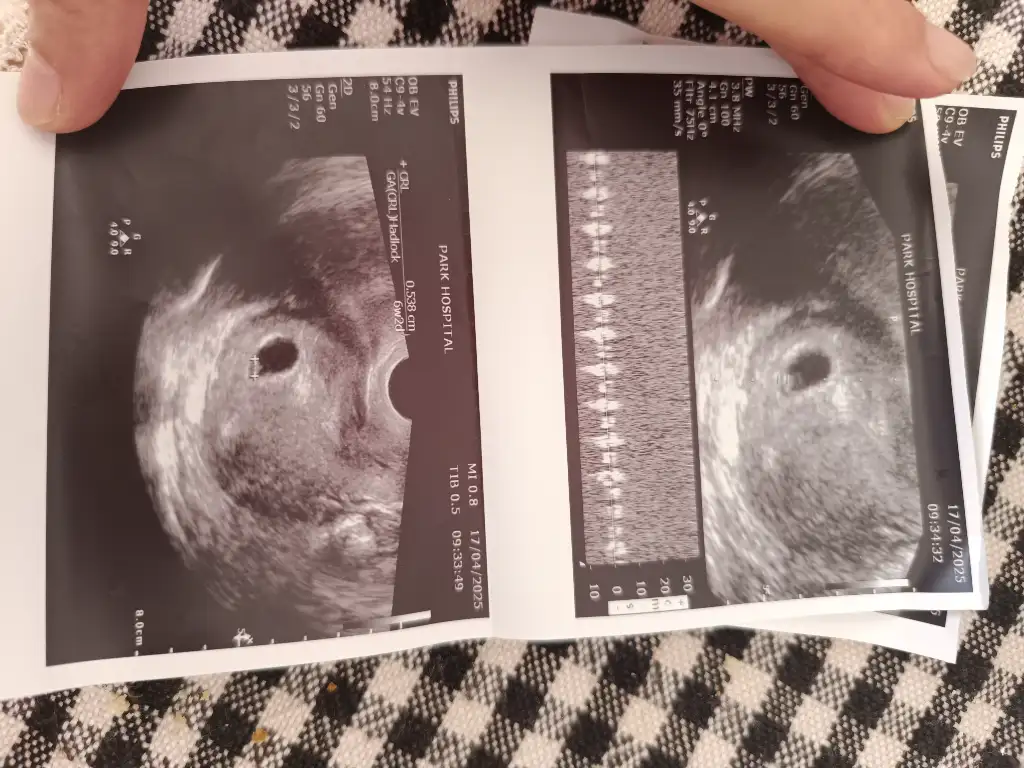

6 haftalık alttan muayene görüntüsü, yorumlayabilir misiniz lütfen

Eklentiler

• 1000138723.webp

Ay benimkini de yorumlar mısınız vajinal USG 😇

• IMG_20250417_154945.webp

IMG_20250417_154945.webp

62,1 KB · Görüntüleme: 82